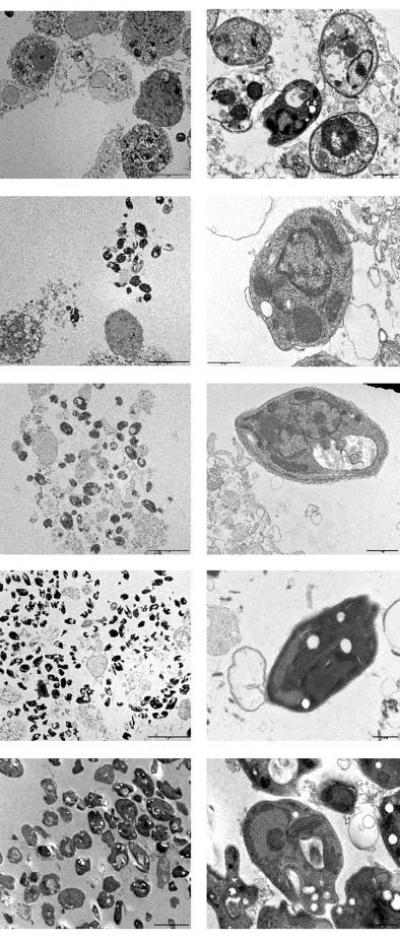

Researchers have developed a clever method to purify parasitic organisms from their host cells, which will allow for more detailed proteomic studies and a deeper insight into the biology of organisms that cause millions of cases of disease each year.

Many infectious pathogens, like those that cause Toxoplasmosis or Leishmaniases , have a complex life cycle alternating between free-living creature and cell-enclosed parasite. A thorough analysis of the proteins that help these organisms undergo this lifestyle change would be tremendously useful for drug or vaccine development; however, it's extremely difficult to separate the parasites from their host cell for detailed study.

As reported in the September Molecular & Cellular Proteomics , Toni Aebischer and colleagues worked around this problem by designing special fluorescent Leishmania mexicana (one of the many Leishmaniases parasites). They then passed infected cells through a machine that can separate cell components based on how much they glow. Using this approach, the researchers separated the Leishmania parasites with only about 2% contamination, far better than current methods.

They then successfully identified 509 proteins in the parasites, 34 of which were more prominent in parasites than free –living Leishmania . The results yielded many characteristics of these organisms, such as a high presence of fatty acid degrading enzymes, which highlights adaptation to intracellularly available energy sources. The identified proteins should provide a good data set for continued selection of drug targets, and the success of this method should make it a good resource for other cellular parasites like malaria.